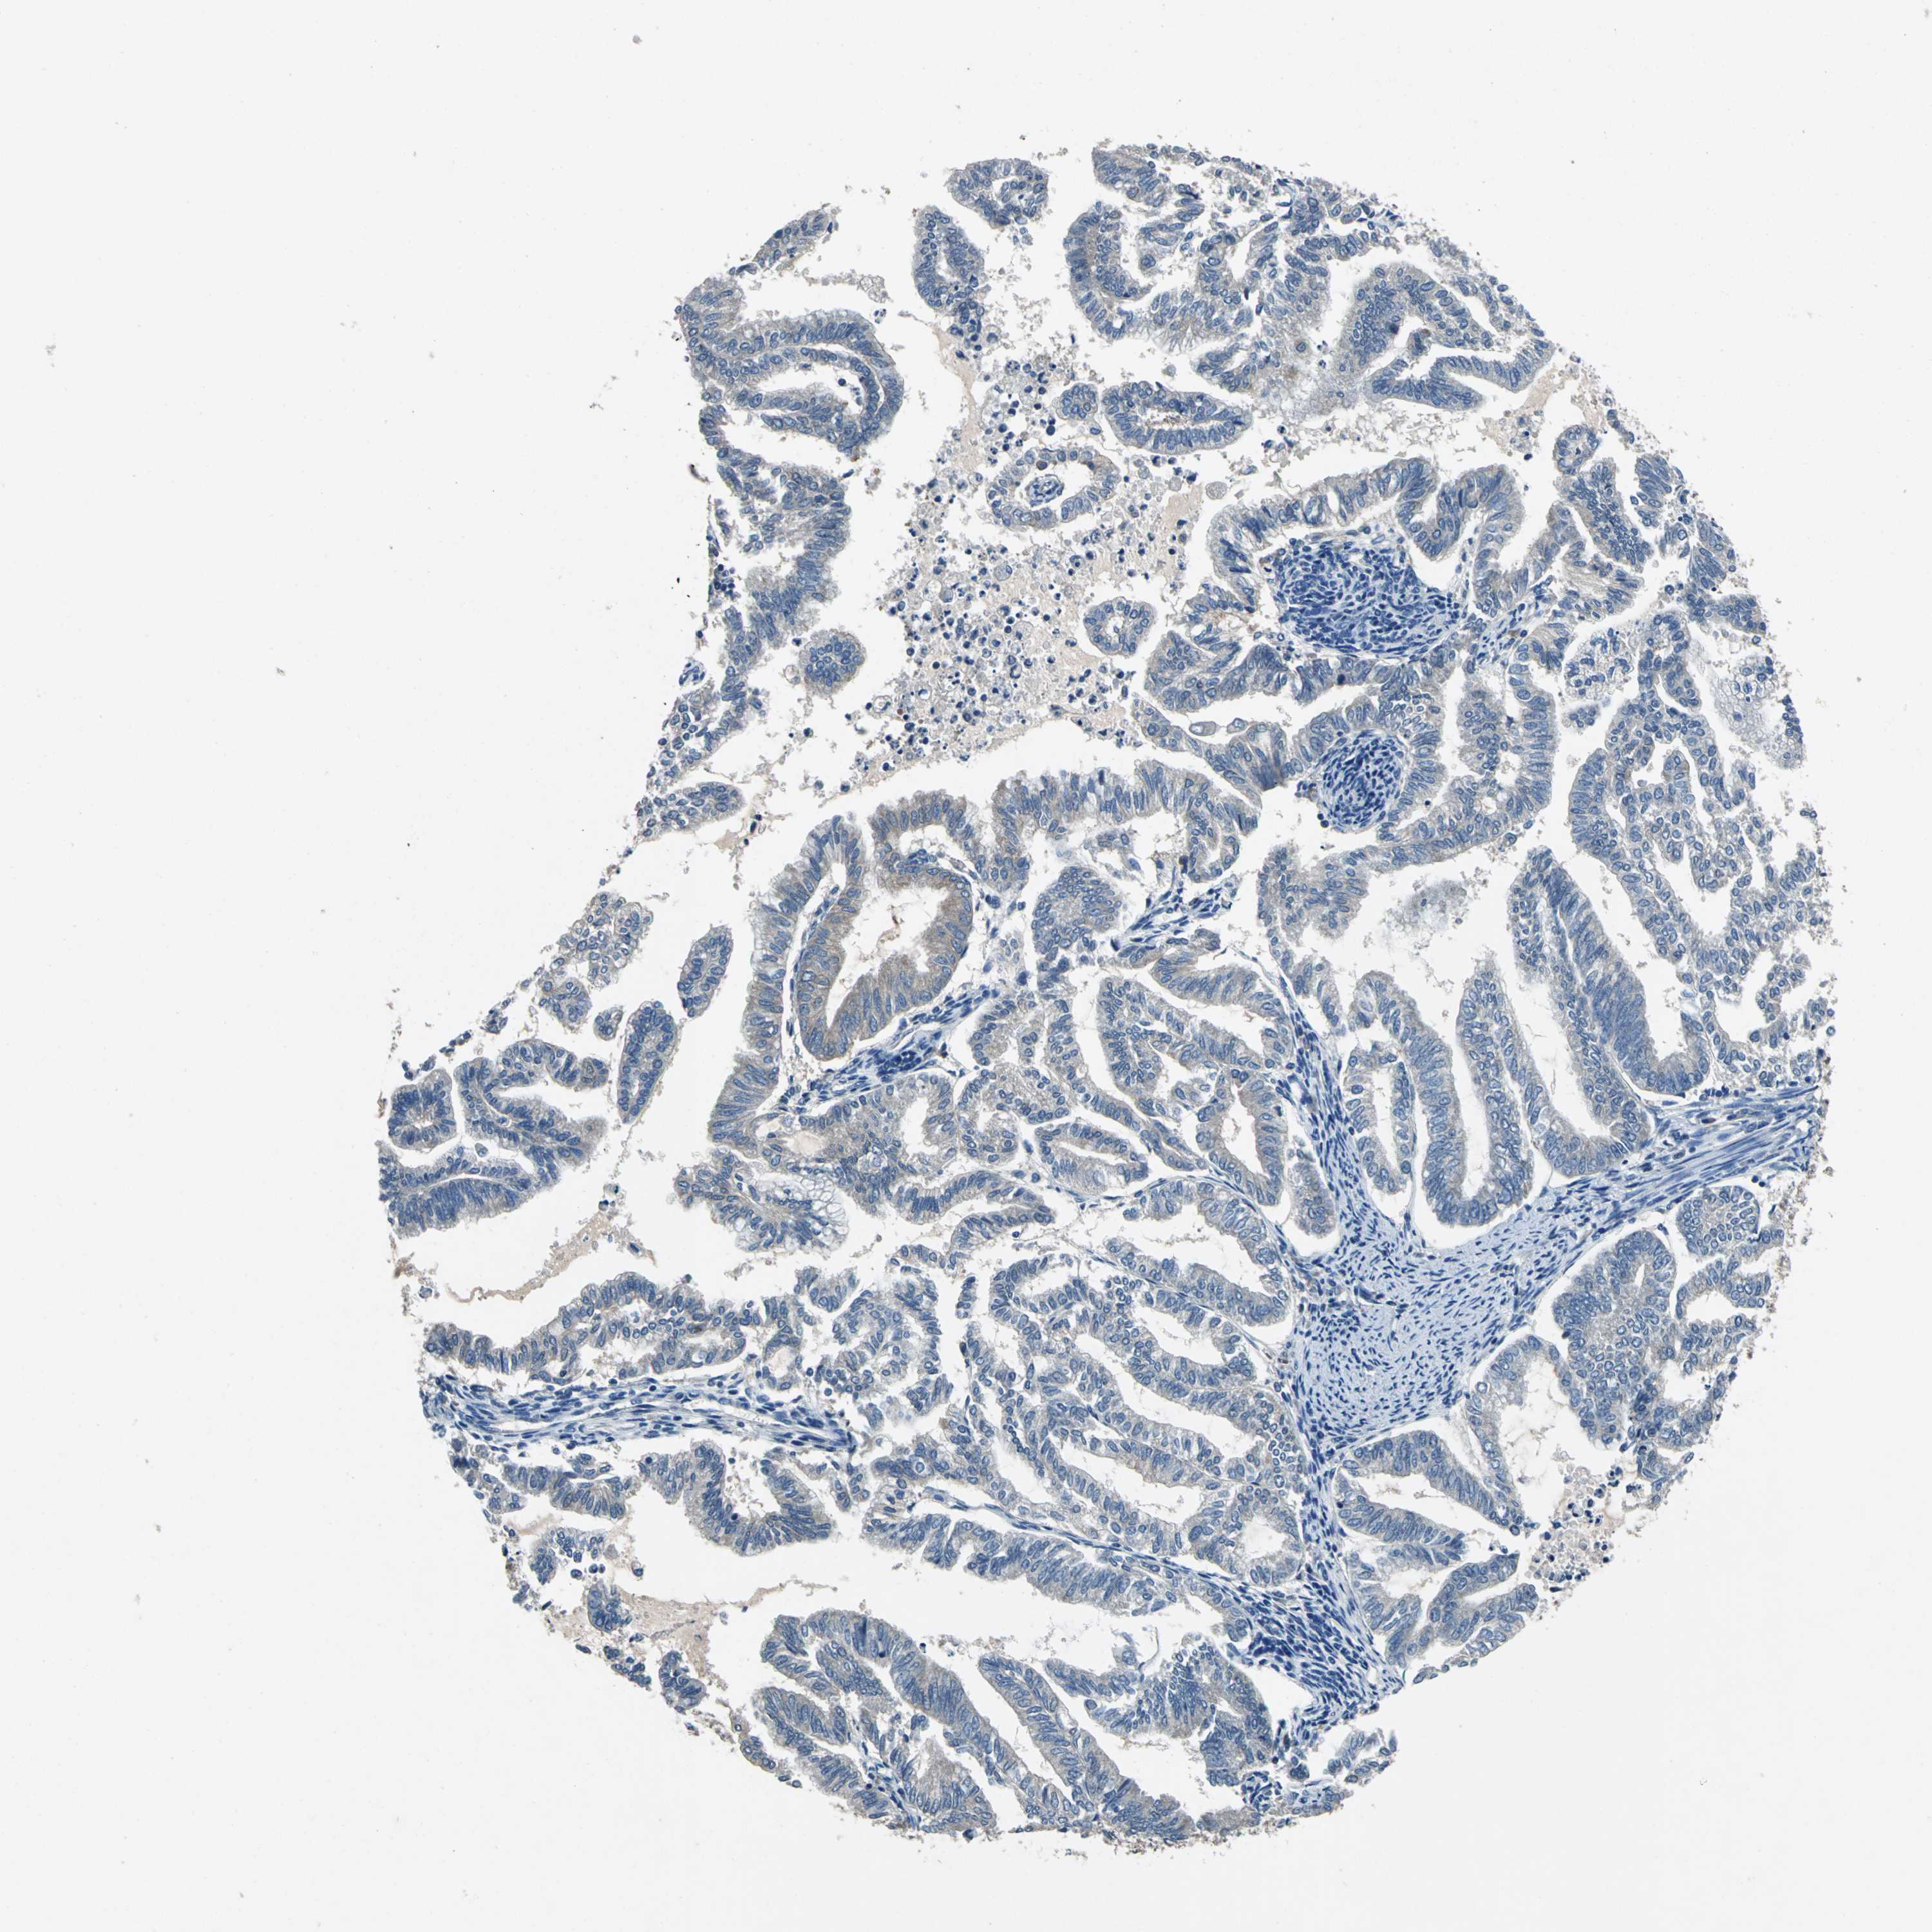

ENDOMETRIAL CANCER - Protein expressioni

A mouse-over function shows sample information and annotation data. Click on an image to view it in a full screen mode. Samples can be filtered based on level of antibody staining by selecting one or several of the following categories: high, medium, low and not detected. The assay and annotation is described here.

Note that samples used for immunohistochemistry by the Human Protein Atlas do not correspond to samples in the TCGA dataset.

Antibody stainingi

Antibody staining in the annotated cell types in the current human tissue is reported as not detected, low, medium, or high, based on conventional immunohistochemistry profiling in selected tissues. This score is based on the combination of the staining intensity and fraction of stained cells.

Each image is clickable and will lead to virtual microscopy that enables deeper exploration of all samples and also displays staining intensity scores, fraction scores and subcellular localization as well as patient and tissue information for each sample.

Antibody HPA006563

Antibody HPA006564

Antibody CAB003844

Antibody CAB016290